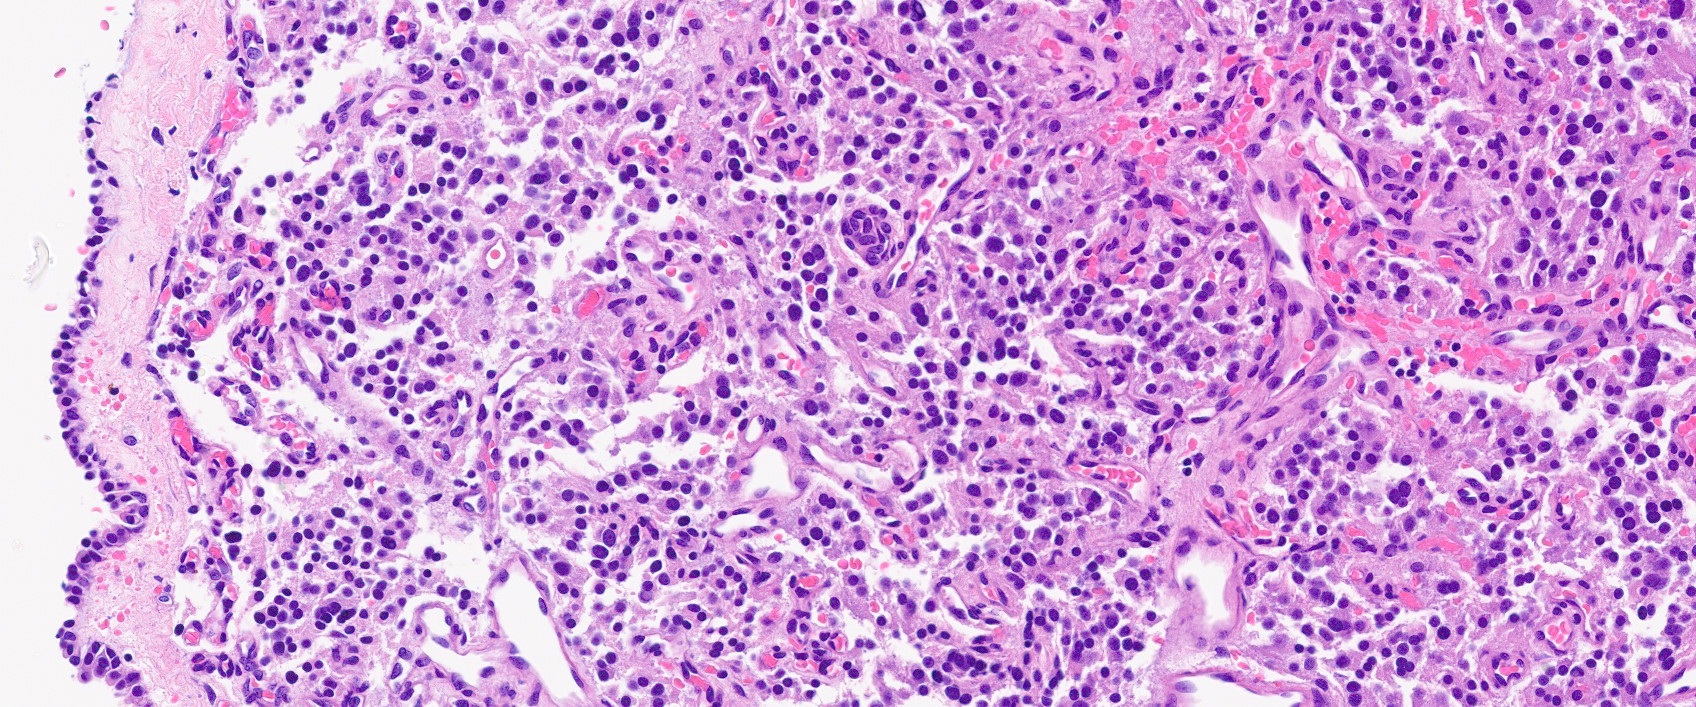

Microscopic (histologic) description

- Prevailing histologic pattern: epithelioid chief cells arranged in distinctive clusters / nests (zellballen pattern), separated by prominent fibrovascular stroma (J Clin Med 2018;7:280)

- Trabecular pattern: ribbons or cords of epithelioid cells divided by fibrous bands

- Other patterns: pseudorosette, angioma-like, spindled and sclerosing

- Chief cells: round, oval to polygonal cells with abundant granular basophilic, eosinophilic or amphophilic cytoplasm (Surg Pathol Clin 2019;12:951)

- Intracytoplasmic hyaline globules may be present in sympathoadrenal paragangliomas

- Giant multinucleated cells and bizarre cells can be present (Srp Arh Celok Lek 2002;130:7)

- Rarely, elongated and spindle shaped cells with a sarcomatoid appearance may be found

- Scattered ganglion cells can be seen

- May have nuclear atypia

- May have dysmorphic vessels, melanin-like pigment (neuromelanin) (pigmented paraganglioma), amyloid, abundant stroma and osseous metaplasia (Diagn Pathol 2012;7:77, Hum Pathol 1992;23:33)

- No or rare mitotic figures except in highly aggressive rapidly proliferating lesions

- May have focal chronic inflammatory infiltrate

- Necrosis is unusual except in patients who have undergone preoperative tumor embolization

Microscopic (histologic) images

Contributed by Luvy Delfin, M.D. and Sylvia L. Asa, M.D., Ph.D.